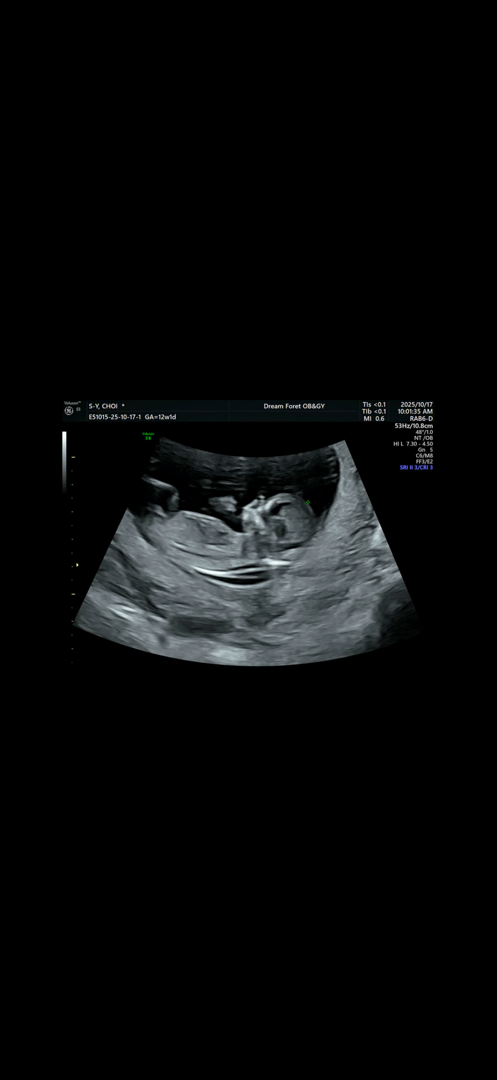

12주인데 성별이 궁금해서요 한번 봐주세요 각도법 을 잘 몰라서요

안녕하세요 엄빠님! 베이비빌리입니다. 각도법이 궁금하신 엄빠님께만 알려드려요🙋🏻♀️🙋🏻♂️ 각도법에 관심 있는 엄빠들이 모여있는 게시글에서 의견을 나누어보면 어떨까요?👼🏻 또, 빌리AI로 각도법을 검사하는 미니 테스트 서비스도 오픈 되었다는 깜짝 소식이 두두등장! 지금 바로 각도법으로 울 아기 성별을 추측해보세요😍 👉🏻 지금 바로 성별 질문 남기기 https://app.babybilly.app/60e1ts ⭐빌리AI로 각도법 검사하는 미니 테스트 서비스 오픈! https://gender-test.babybilly.co/ 한 번 무료로 검사해보시고 결과가 잘 맞는지 빌리에게도 알려주시기로, 약-똑!😍